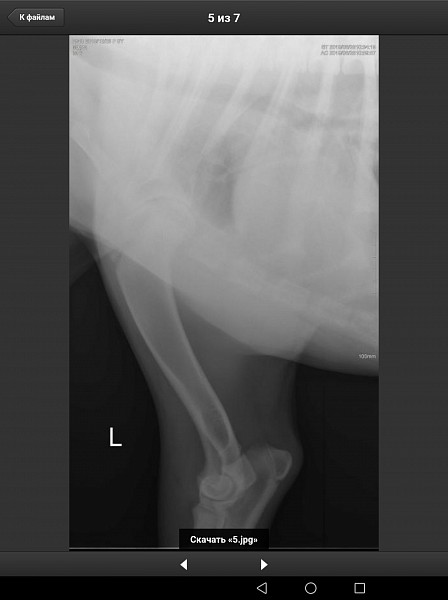

У нас немецкий дог, девочка, 6 месяцев, привита по возрасту. Поставлен диагноз Расслаивающий остеохондрит плечевого сустава (мышь плечевого сустава). Сказали, нужна операция по зачищению этого сустава. Как можно скорее.

Есть рентгеновский снимок. Прошу вас прокомментировать его, правильный ли диагноз? Как срочно нужно оперировать, если подтвердится диагноз? Какой период реабилитации? И, что нас ожидает в будущем, от чего могла развиться болезнь, наследственное это или нет, что делать, чтобы предупредить заболевание суставов других лап?

Здравствуйте. Судя по описываемым вами симптомам у собаки, действительно имеется поражения хрящевой поверхности какого-то сустава грудой конечности. На предоставленных вами снимках, затруднительно тщательно рассмотреть суставные поверхности. Ярко выраженной патологии хряща (расслаивающий остеохондрит не просматривается). Для подтверждения или исключения данной патологии наиболее оптимальным является компьютерная томография. При подтвтерждении диагноза, основным методом лечения является хирургическое вмешательство, направленное на устранение фрагментированного участка хряща и зачищении дефекта для формирования на месте поражения волокнистого хряща.